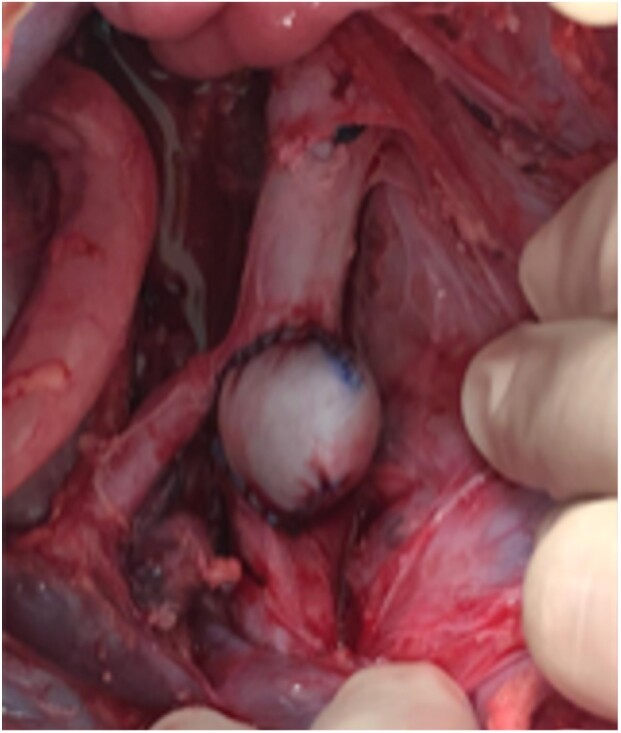

Methods: A total of 18 swine underwent a surgical procedure to create a TAA. An autologous peritoneal patch was used to create the aneurysm in 2 animals, and a bovine pericardial patch was used in the other 16. The animals were followed up postoperatively, and the aneurysm sac was reexamined after 4 weeks. The animals that did not die in the post-operative period were euthanized according to institutional recommendations.

Results: All of the animals underwent laparotomy with retroperitoneal access. Two received an autologous peritoneal patch and 16 received a bovine pericardial patch. Three animals underwent single suprarenal clamping, while 15 underwent sequential clamping. There were no differences in operative time (p=0.207) or total clamping time (p=0.276) between groups. There was a higher mortality rate after 4 weeks in animals that received single clamping (100%) than sequential clamping (26.7%) (p=0.0017).

Conclusions: The experimental model of TAA using a bovine pericardial patch and a sequential clamping technique provided a stable and reliable platform that remains stable and patent for up to 4 weeks. This model can be extremely valuable for assessing new endovascular therapy options in living organisms.